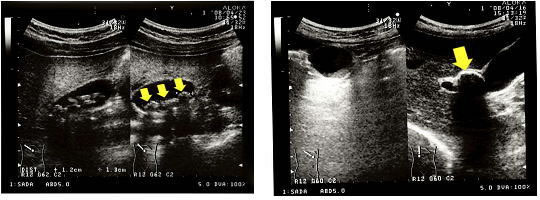

胆のう結石症の診断には腹部(左の図の緑円の部分)の検査を行います。

最も負担なく胆のうの状態や結石を直接みることができます。 ただし食事後や肥満体型の方は診断が難しくなります。